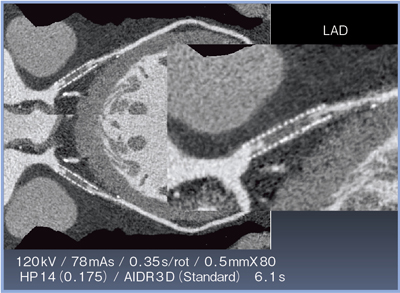

MIP画像ではノイズの低減が確認できるとともに,RCAの末梢や細い血管領域が明瞭に描出されていることが確認できる(図4)。

図4 AIDR 3Dの有無による比較(MIP画像)

図5に示すように,ノイズが大きく低減されても,CT値は変わらないことから,コントラスト比(CNR)が保たれていることがわかる。

当院では,CTで冠動脈をフォローアップしている症例について,64列CTとAquilion PRIMEで同一条件で撮影した場合のDLP値の比較検討を行った。CABG術後のフォローアップ症例と,冠動脈のみを撮影した症例の全例で,Aquilion PRIMEの方がDLP値が低く,平均で44%の被ばく低減が実現していることが認められた(図6)。冠動脈のみの撮影で比較すると49%と,被ばく量は,ほぼ半減している。

![]() 図5 AIDR 3Dの有無によるCNRの比較(MPR画像) |

![]() 図6 64列CTとAquilion PRIMEの被ばく低減効果の比較 |